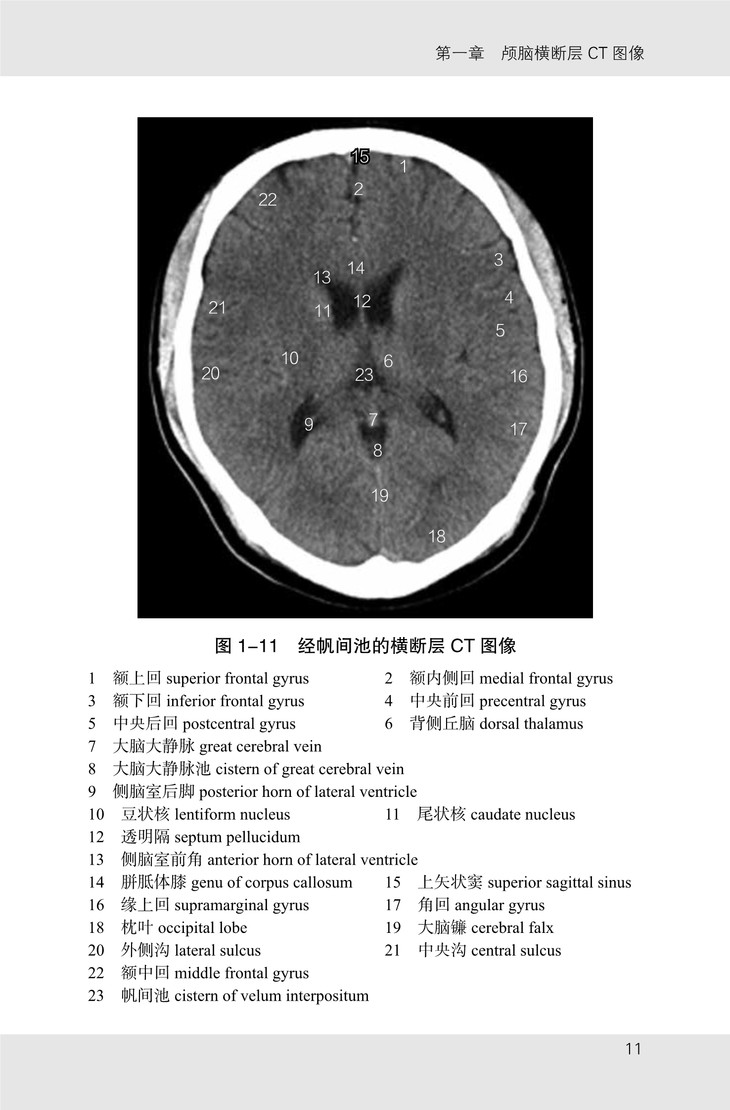

《颅脑影像解剖图谱》共有图像 175 幅,包括以下四个部分:

(1)颅脑 CT 图像,从颅顶至枕骨大孔共有横断层图像 21 幅,扫描基线为眦耳线;